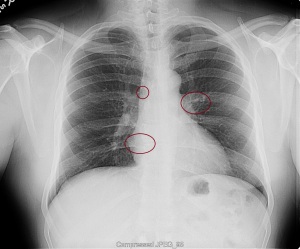

“My family and I have been the subjects of Government funded human research and/or hate crimes. These crimes are being covered-up by using the words National Security. The fact that my two minor children have the same and/or similar devices in their little bodies speaks for themselves. My sons were ages 3 and 4 when the discoveries took place. Their x-rays, blood & urine analysis present the true facts. The devices can only be introduced into the body, while being in a medical facility. All three of us were patient of the same defendant hospital.

“Please take a look at both X-rays. Superimpose the foreign objects AKA EKG clamps and you will find that they are the same devices. when have you ever seen an EKG clamp place sideways in the abdomen? Both x-rays have been confirmed by Radiologist Louis Teresi as having foreign body reactions in the abdomen, right and left flanks.

“The obvious implant in the 2012 x-ray stands out from the others, because it at the time had not embedded into my flesh (heart).”